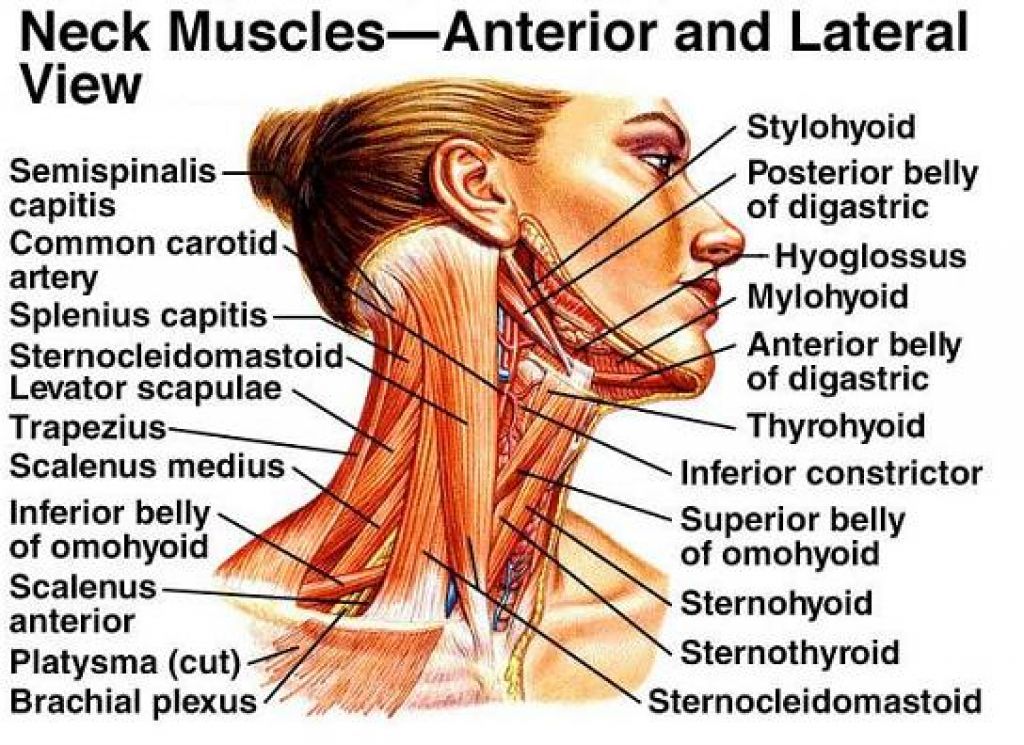

People with arthritis often will avoid physical activity in the affected joint because of the pain. A physical therapist can help with working the joint stiffness without damaging it. A physical therapist can help achieve a good range of motion which may include building strength in the muscles surrounding the affected joint stabilizing the weakened joint. They will usually create an exercise program for you. Exercise is a big part of occupational therapy being effective.